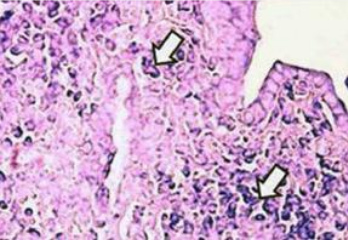

Microfotografía de pulmón de rata intoxicada por

antracenonas de una planta silvestre [11]

La acumulación de toxinas entre el capilar y las

células determinará:

Los radicales ácidos libres en el espacio

intersticial forman una barrera y destruyen los

nutrientes. Así bloquean el oxígeno y no llega

oxígeno más a las células.

El efecto cáustico [ätzend] de los ácidos

Los residuos ácidos son agresivos con un efecto

cáustico [ätzend] y pueden quemar la propia

célula:

-- ácido úrico [Harnsäure]

-- ácido oxálico [Oxalsäure]

-- ácido carbónico (CO2)

-- ácidos grasos (colesterol) etc.

Además los ácidos tienen reacciones con los

nutrientes y les convierten en substancias menores

degradándoles. Así la célula solo recibe

nutrientes degradados, o no recibe nada de todo

porque los nutrientes no pueden pasar la barrera

de ácidos en el espacio intersticial más.

Fibrosis pulmonar: demasiado gas carbónico [Kohlensäure]

- el ácido destruye a la célula

Por ejemplo si buscamos el origen de la fibrosis pulmonar

[nota3],

Nota 3: La fibrosis pulmonar es una condición

en donde el tejido profundo de sus pulmones se va

cicatrizando. Esto hace que el tejido se vuelva grueso y

duro. Esto dificulta recuperar el aliento [la

respiración] y es posible que la sangre no reciba

suficiente oxígeno.

entonces podríamos explicar que en condiciones normales el

pulmón recibe oxígeno y trata de evacuar el anhídrido

carbónico (Kohlendioxid, CO

2) en cada ciclo

respiratorio, pero los problemas empiezan con el pulmón

cuando hay más gas carbónico [Kohlensäure] de lo que puede

eliminar el pulmón, terminado por ello empantanado de

ácido, el ácido destruye a la célula. Eso pasa en todos

los órganos: hígado, riñón; etc.